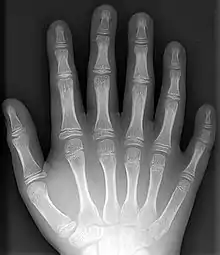

حالة كثرة الأصابع تظهر بواسطة الآشعة السينية

- كثرة الأصابع: أصابع قدم إضافية أو أصابع يد إضافية